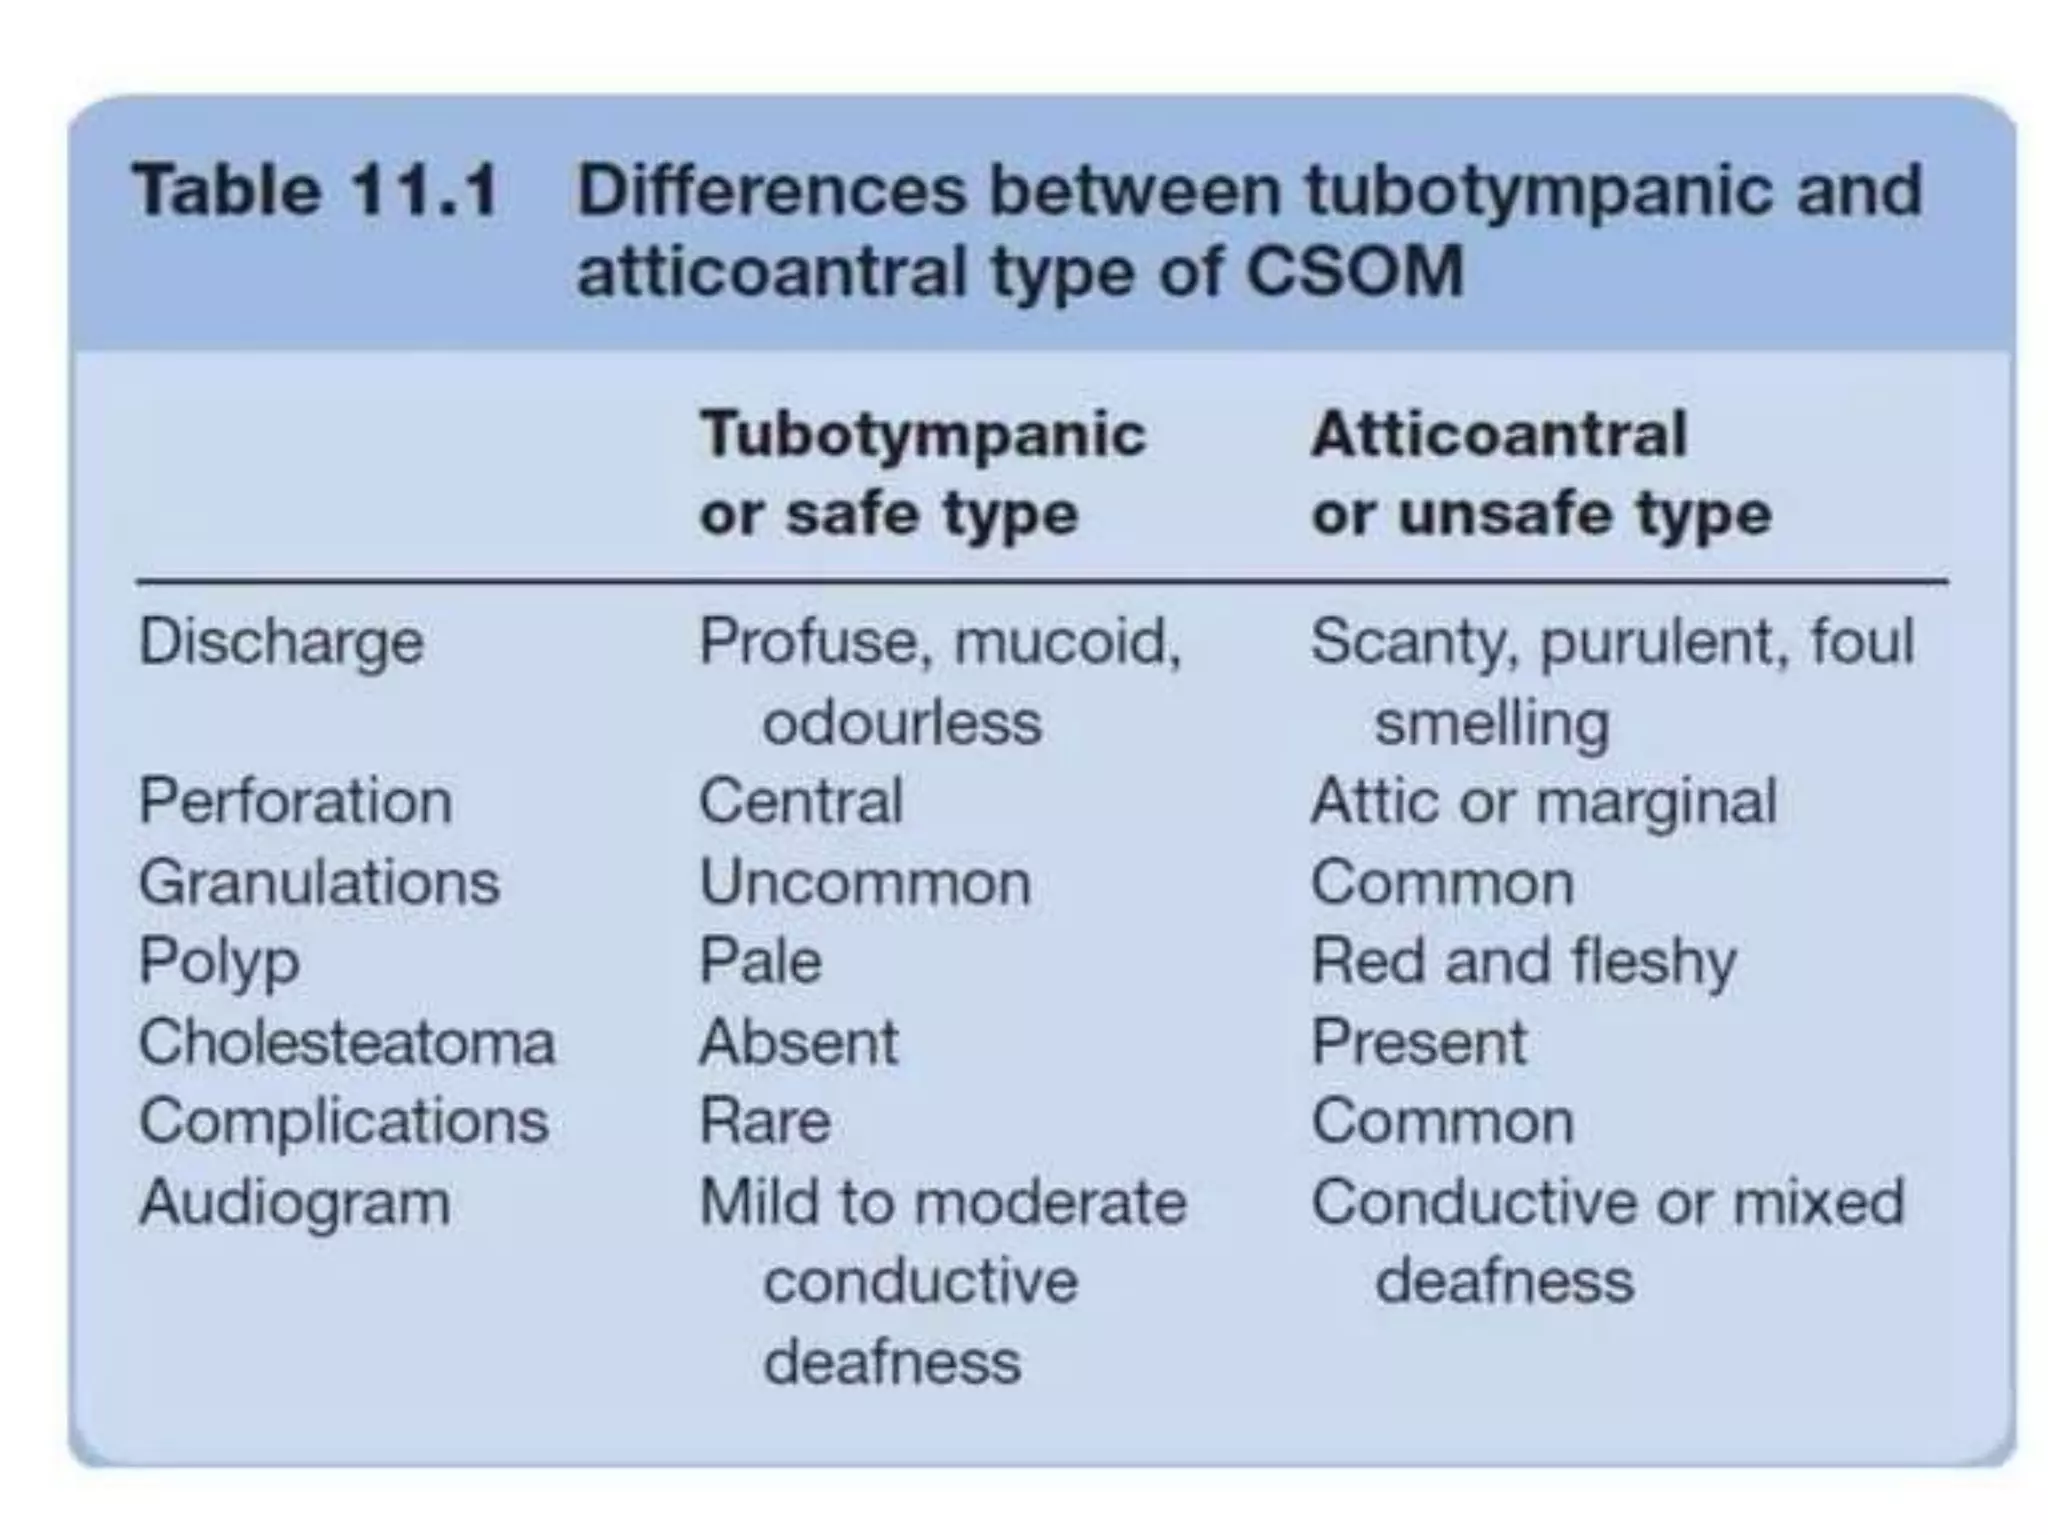

Chronic otitis media is a chronic inflammation of the middle ear and mastoid cavity that presents with recurrent ear discharge through a perforated eardrum. It has several subtypes depending on the state of the eardrum perforation and epithelium. It can be caused by prior acute otitis media, genetics, environment, eustachian tube issues, gastroesophageal reflux disease, craniofacial abnormalities, or immune deficiency.